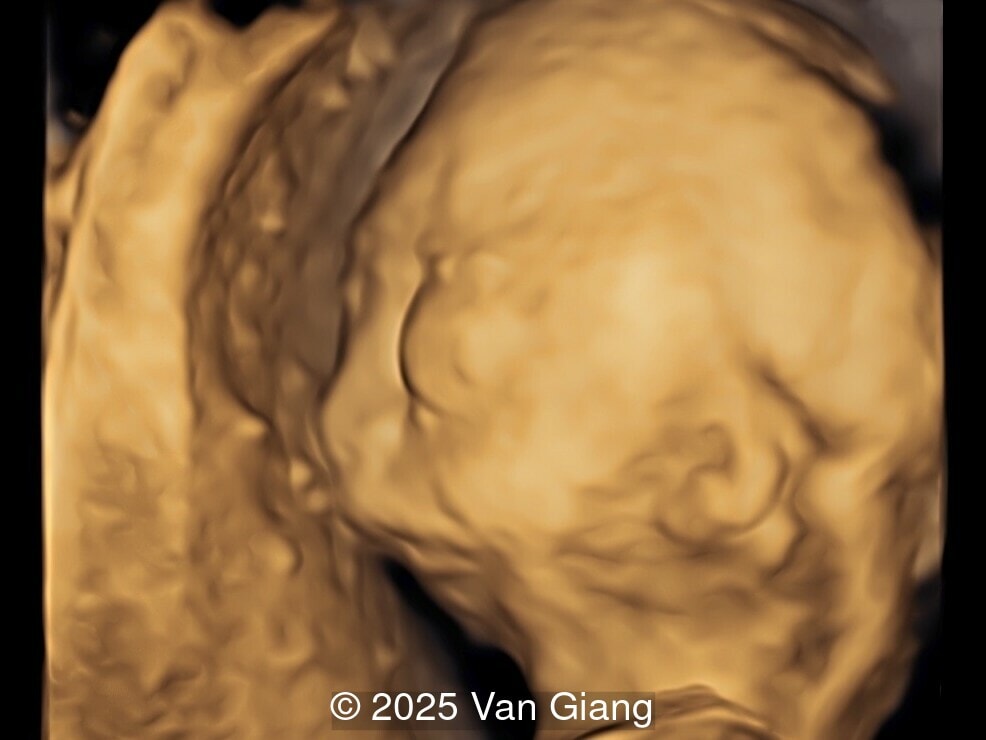

A 32-year-old primigravida presents at 20 weeks gestation without first trimester screening. Ultrasound reveals a small for gestational age fetus with the following anomalies:

Ultrasound revealed severe mandibular and zygomatic hypoplasia, glossoptosis, cleft palate, and micrognathia with an abnormal facial profile. Both upper limbs showed radial ray sequence with abnormal thumbs and shortened forearms. Unilateral clubfoot was also noted. No major cardiac or visceral anomalies were observed. Based on these findings, Nager syndrome was suspected.

fetal profile

Image 1 fetal profile